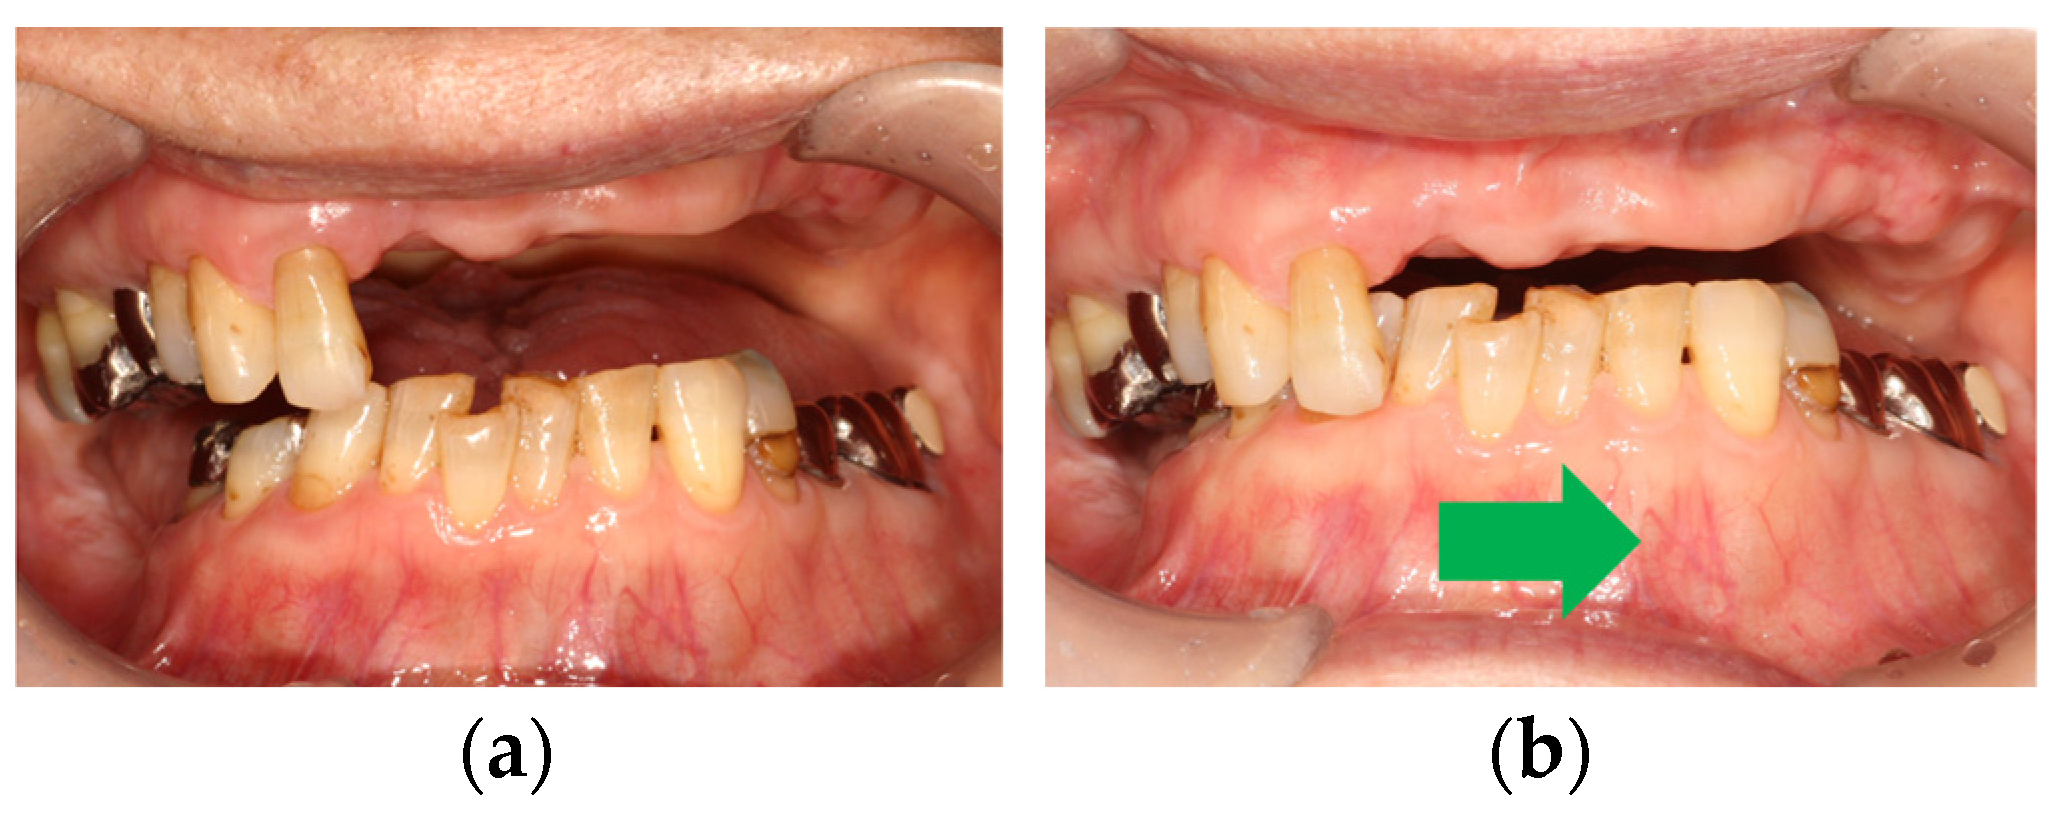

Maxillomandibular registration is an important procedure to manage anterior hyperfunction and combination syndrome. To control anterior hyperfunction, the absence of anterior tooth contacts is key for the stability of maxillary removable prosthesis [27]. When patients have flabby hyperplastic tissues, the mobility of the record base with an occlusion rim should be examined carefully, even if a specific procedure was conducted during the maxillary impression described above. Flabby tissues at the anterior site enhance vertical displacement or rotation, and it is better to avoid or minimize occlusal force at the anterior site during maxillomandibular registration [23]. Daher et al. introduced methods to obtain maxillomandibular registration and definitive impressions in a single visit [24]. This report used a maxillary impression tray with an anterior window for impression and maxillomandibular registration. This anterior window can avoid occlusal force at the anterior site because there is no occlusion rim at the anterior site. However, an anterior occlusion rim is necessary to decide the position of the maxillary anterior teeth and lip support. In anterior hyperfunction patients, anterior occlusal contact during maxillomandibular registration should be considered to avoid the displacement of the maxillary anterior occlusion rim by the mandibular anterior teeth. It is recommended that maxillomandibular registration is conducted using only posterior occlusal contacts as much as possible. Maxillomandibular registration in Eichner B4 patients should be conducted with careful attention at anterior occlusal contact. Patients with anterior hyperfunction sometimes show anterior migration of maxillary anterior teeth and reestablishment of proper VDO is essential. Anterior occlusal contact, especially at the canine, occasionally causes premature contact, inducing an improper lateral shift of the mandible; so, proper maxillomandibular registration should be considered (Figure 6).

Figure 6. Lateral shift of mandible after first teeth contacts: (a) first teeth contact; (b) mandibular lateral shift (left side) of mandible after first contact (green arrow). Source: the authors.